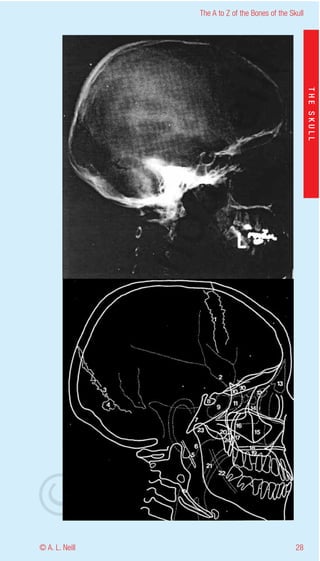

The A to Z of the Bones of the Skull

External Skull Lateral / oblique

eill

radiology

THE SKULL

1           Coronal suture

2           Impression for Middle meningeal artery

3           Lambdoid suture

aN

4           Wormian bone - Extrasutural bone

5           Styloid process

6           Posterior wall of Nasopharynx

7           Clivus - (base of Sphenoid and Occiptal bones)

8           Hypophyseal fossa

9           Sphenoid sinus

nd

10          Greater wing of the Sphenoid

11          Posterior Air cells in the Ethmoid - Ethmoid sinus

12          Anterior Air cells in the Ethmoid - Ethmoid sinus

13          Frontal sinus

14          Zygoma - frontal process

ma

15          Maxilla - malar process

16          Zygoma - Arch

17          Posterior border of the Maxillary sinus

18          Hard palate - Palatine bone

19          Alveolar bone in Maxilla

rA

20          Pterygoid plates

21          Soft tissue of Soft Palate and Uvula

22          Mandibular canal

23          Head of Mandible

24          Coronoid process of Mandible

©D